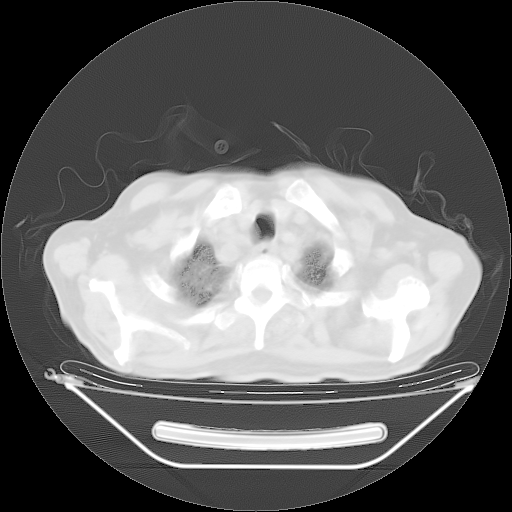

今天复查肺部CT,发现双肺广泛磨玻璃样改变。所以我把3月19日和5月9日相隔50天的肺部CT上传。请大家会诊。

2009年3月19日肺部CT片。

5月9日肺部CT(在4月27日齐鲁医院肺部CT描述部分肺组织磨玻璃样改变,12天后肺组织广泛磨玻璃样改变)